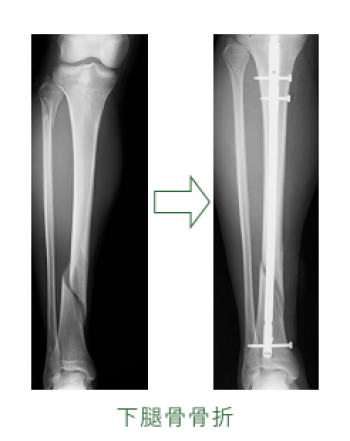

º£Æü¡¢¤´¾Ò²ð¤¹¤ë¤Î¤Ï¡¢²¼Âܹü¹ü´´Éô¹üÀޤˤĤ¤¤Æ¤´¾Ò²ð¤·¤Æ¤¤¤­¤Þ¤¹¡£

²¼Âܹü¹ü´´Éô¹üÀÞ

¸òÄÌ»ö¸Î¡¢¥¹¥Ý¡¼¥Ä¾ã³²¤È¤·¤Æ¤è¤¯¤ß¤ë¹üÀޤǤ¹¡£

¥é¥ó¥Ê¡¼¡¢¥Ð¥¹¥±¥Ã¥È¥Ü¡¼¥ë¡¦¥Ð¥ì¡¼¥Ü¡¼¥ë¤ÎÁª¼ê¡¢¤¦¤µ¤®Ä·¤Ó¤Ê¤É¤Çæú¹ü¤Þ¤¿¤Ï礹ü¤ËÈèÏ«¹üÀÞ¤¬¤ß¤é¤ì¤ë¡£

¿¤¯¤Î¹üÀÞ¤Ïæú¹üÃæ¡¦²¼1/3¤Î¶­³¦Éô¤Ëµ¯¤³¤ê¡¢æú¹ü¤¬¹üÀÞ¤¹¤ë¤È礹ü¤â¤³¤ì¤Ëȼ¤Ã¤Æ¹üÀÞ¤¹¤ë¡£

³«ÊüÀ­¹üÀޤˤʤê¤ä¤¹¤¯¡¢¹üÌþ¹ç¤¬¤·¤Ë¤¯¤¯¡¢È¿Ä¥²¼ÂܤʤɤÎÊÑ·Á¤ò»Ä¤¹¤³¤È¤¬Â¿¤¤¡£